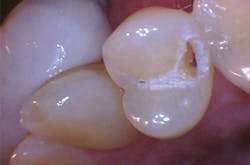

The removal of dental hard tissue is accomplished by what is known as thermomechanical photon-induced water-mediated ablation, which is a process in which the micro-explosive force of photons on water droplets results in the selective removal of carious dentin (figures 2a–2d). The laser energy seeks out tissue with higher water content, such as a carious lesion, and evaporates it without contact, vibration, or the introduction of microfractures, leaving the surrounding healthy enamel and dentin intact.

Figures 2a–2d: A Class II posterior cavity preparation